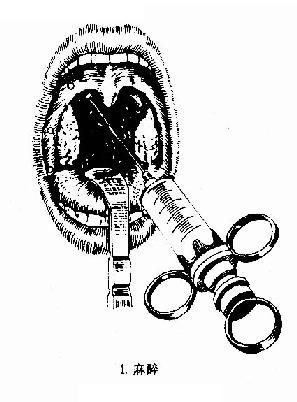

1.麻醉及体位:采用局部麻者,取坐位或半坐位,咽反射敏感者可于咽部喷1%的卡因,再以1%奴夫卡因(加1:1000肾上腺素)于舌腭弓及咽腭弓粘膜下及扁桃体外侧包膜周围浸润麻醉

图6-2 扁桃体切除术(剥离法)

3.全身麻醉时,病人仰卧头后仰位,肩下垫一小枕,摇低手术床,使头部稍低于胸部,避免术中将血液吸入气道。置入台维氏式开口器,注意勿压伤舌及口唇,勿压落牙齿。